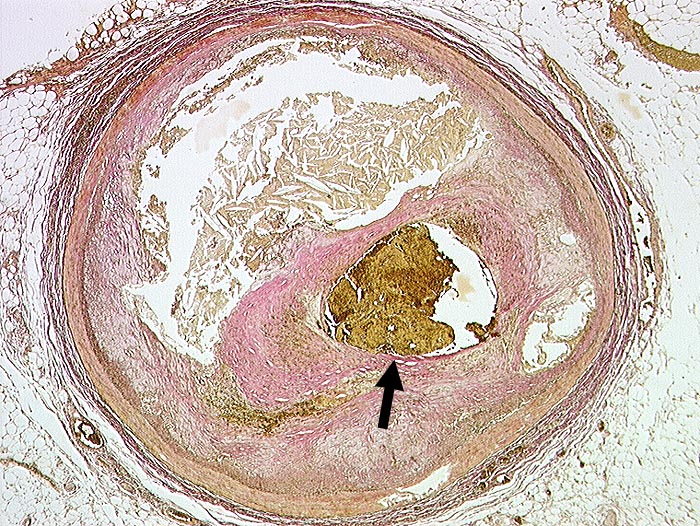

Koronarthrombose

vaskulär / Durchblutungsstörung

Arteria coronaris

Kardiovaskuläres System

Exzentrische Stenose von mehr als 75% des Lumendurchmessers. Atherom mit herausgelösten Cholesterinkristallen. Intraluminale frische Thrombose.

Transmuraler akuter Myokardinfarkt mit Myokardruptur bei thrombotischem Verschluss des RIVA.

Diabetes mellitus Typ II und Adipositas.